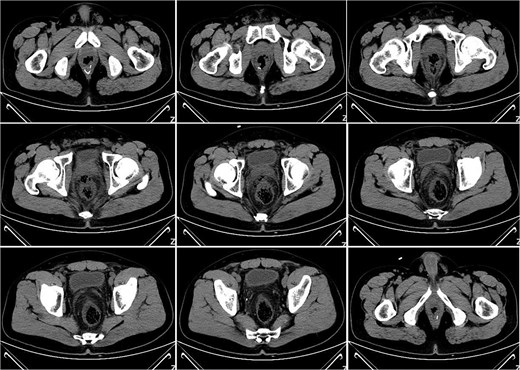

On postoperative Day 7, the patient developed a fever (38.5°C) and mild lower abdominal discomfort. Laboratory tests revealed leukocytosis (white blood cell count: 16.06 × 109/l, neutrophil percentage: 89.1%). A pelvic computed tomography (CT) scan suggested cystitis (Fig. 1). Anti-infective therapy with intravenous cefoperazone sodium and sulbactam sodium was initiated. The patient’s vital signs, complete blood count, and temperature were closely monitored.